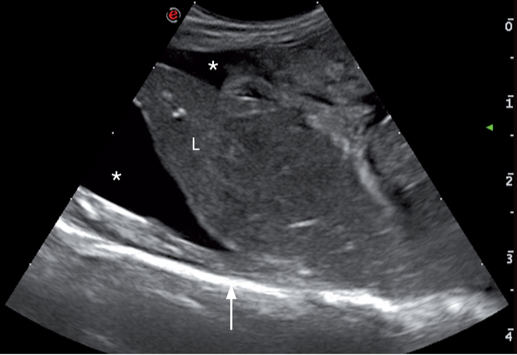

腹膜后间隙积液可能是由于肾上腺,肾,输尿管,大血管和淋巴干的损伤造成的(图12.)。液体可能为血液,尿液,漏出液或改良性漏出液。需要穿刺才能确定液体的性质。